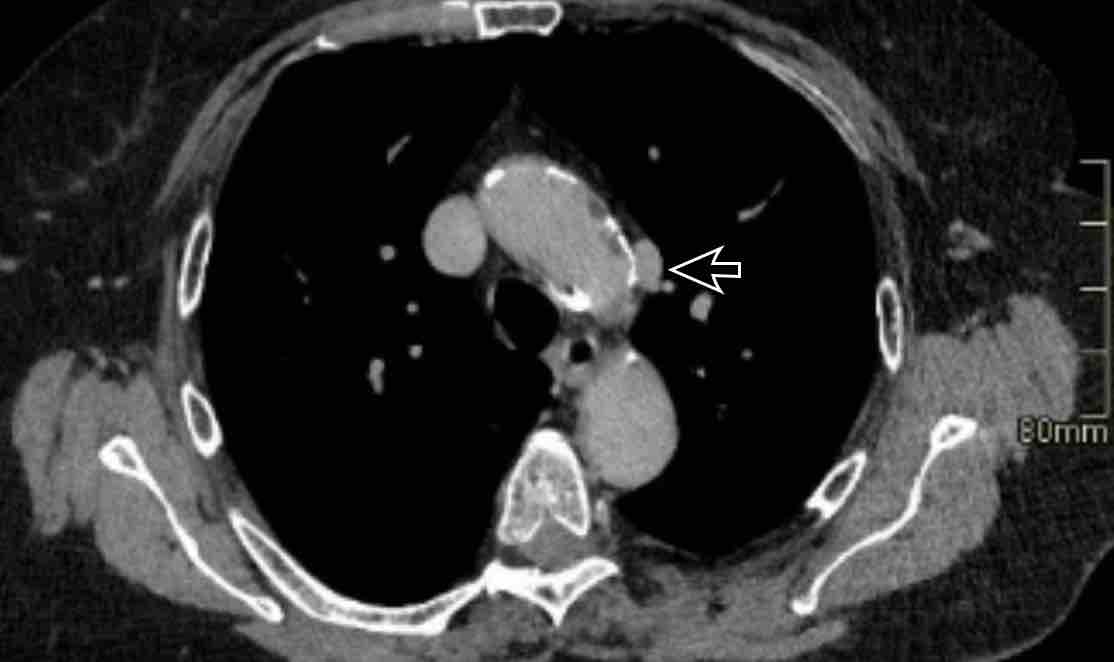

Hình ảnh

PAPVR bên trái phát hiện tình cờ với dẫn lưu trên tim của máu từ thùy trên trái vào tĩnh mạch tay đầu trái (các mũi tên).